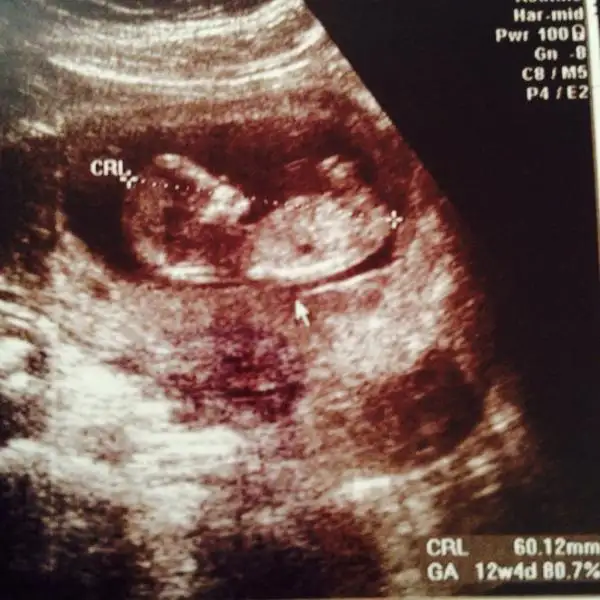

Güzel annişleeeer nasılsınız? Biz bugün ikili teste girdik şükür ölçümlerimiz güzel çıktı. Ana doktorumuz anca 16. haftada söylicem cinsiyet dedi.

Ben de burdan size soriyim dedim usta gözler bi göz atsanız benim limonuma pek bi seviniriz:) 12+4 görünüyoruz burda :)

Hepinize sağlıklı hamişlikler 😘